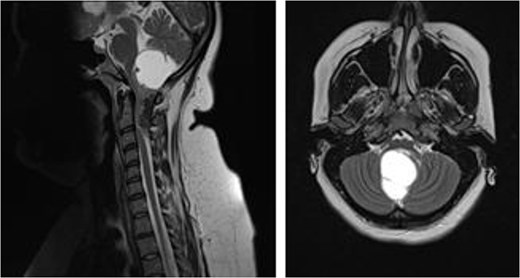

Magnetic resonance imaging brain with gadolinium demonstrated a ring enhancing cystic lesion in the posterior fossa, with solid enhancing extension into the spinal canal down to the C3 level (Fig. 1). The radiological appearance was consistent with an ependymoma.

MRI brain demonstrating cystic posterior fossa mass, with solid component extending past the foramen magnum, down to the level of C3, on sagittal and axial views, respectively.